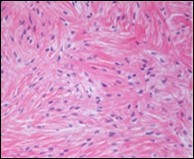

Figure 3.Low grade fibromyxoid sarcoma demonstrating alternating fibrous and myxoid areas comprised of uniform spindle-shaped cells (11).

Macroscopically,the neoplasm is gradually progressive, painless, firm, tan coloured, well circumscribed, grossly infiltrative, soft tissue mass of magnitude varying from one centimetre to 18 centimetres, commonly of 6 centimetres diameter. Cut surface is fibrotic with focal myxoid areas4. On fine needle aspiration cytology, the cellular neoplasm is configured by spindle-shaped cells. Tumour cells contain scant, wispy cytoplasm, uniform, elongated nuclei and miniature, inconspicuous nucleoli. The background is prominently myxoid. Significant nuclear pleomorphism or mitotic activity is absent. However, cogent diagnosis on cytology may be challenging 4.5. On low power, the well demarcated neoplasm is composed of alternating foci of myxoid and fibrous tissue. Giant rosettes are intermingled with zones of whorled cellular aggregates recapitulating preliminary rosettes.

Bland tumour cells depict monotonous, hyperchromatic nuclei. Tumour areas can exhibit prominent curvilinear, arching or plexiform vasculature. Mitotic activity is exceptional 4, 5.

Typically, low grade fibromyxoid sarcoma is comprised of a whorled cellular pattern with intermingled fibrous and myxoid areas. Also, minimally cellular areas of collagenous tissue are denominated, composed of uniform spindle-shaped cells4, 5. Unique morphologic pattern of hyalinising spindle cell tumour configuring giant rosettes can appear in certain low grade fibromyxoid sarcomas4, 5.

The minimally to moderately cellular neoplasm is composed of bland, fusiform or spindle-shaped cells with scarce cytoplasm and angulated nuclei. Also, whorled cellular aggregates are exhibited. Focal to diffuse cellular whorls are intermingled within a dense, collagen-rich stroma. Abrupt, focal transition to myxoid areas can be discerned. Roughly 45% neoplasms depict foci of epithelioid cells. Nearly 40% tumours display enlarged, inadequately configured collagen rosettes2, 4.